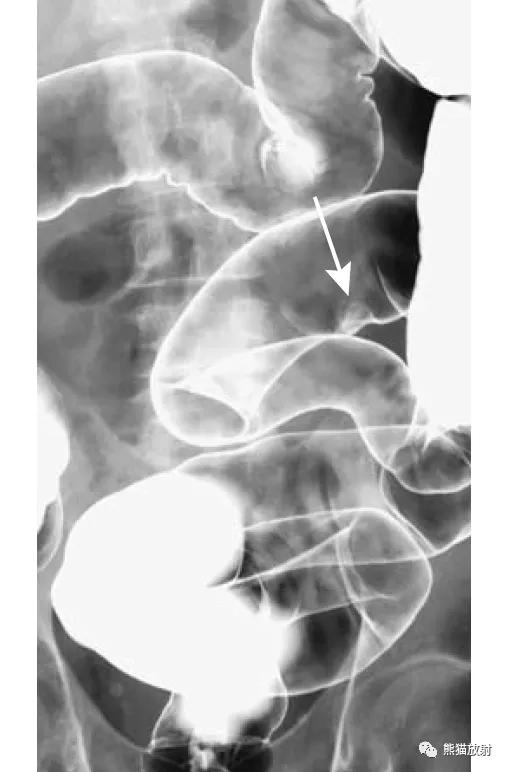

盲肠肠扭转。 盲肠明显扩张并移位至左侧(箭头)。右腹部可见小肠扩张,提示继发小肠梗阻。

盲肠扭转。X线摄片显示中腹部肠管明显扩张(箭头)。钡餐检查示升结肠扭曲部位可见特征性的鸟嘴征(箭头)。

乙状结肠扭转。消化道造影侧视图可见乙状结肠局部走行扭曲(箭头)。

结-结肠肠套叠(箭头)。此例病因很罕见,为结肠子宫内膜异位。

结-结肠肠套叠,由盲肠癌所致。钡灌肠显示横结肠中的肠套叠(箭头),在进一步的压力下,肠套叠移位至升结肠。

回-结肠套叠。CT定位像示7岁患儿的肠套叠(箭头)。Burkitt淋巴瘤所致。右图:10个月大的婴儿,疼痛和右上腹肿块。X线平片示横结肠(箭头)区域有软组织肿块。钡灌肠证实为肠套叠。